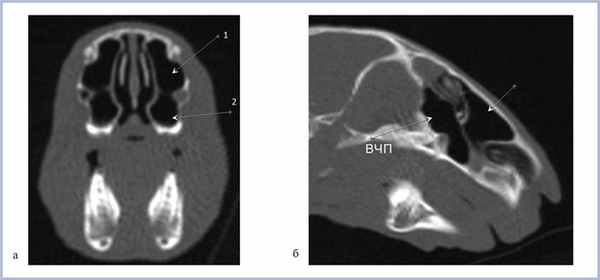

На рис. 2 представлены верхнечелюстные пазухи кролика в возрасте 3 нед в различных проекциях; на рис. 3 в возрасте 6 мес. Таким образом, у кроликов уже в возрасте 3 нед определяются сформированные верхнечелюстные пазухи.

Рис. 3. Компьютерная томография околоносовых пазух кролика в возрасте 6 мес.